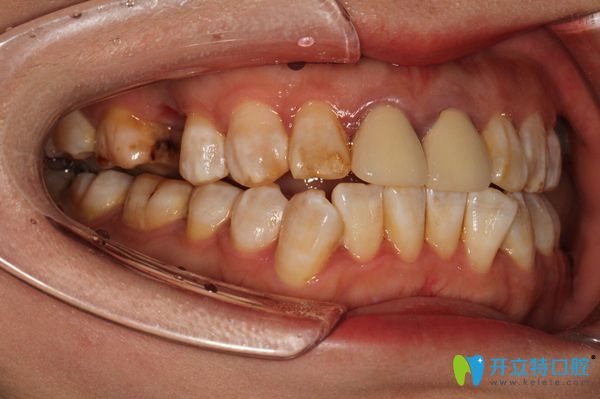

錢女士今年30多歲了,她的上頜右側牙齒在外力的作用下,缺失了一顆牙齒,不僅僅有點影響美觀,更重要的影響正常的咀嚼,還老塞牙。

在術前進行常規(guī)的檢查,拍片對骨質量進行測量及評估,確定擬植入種植體的規(guī)格。